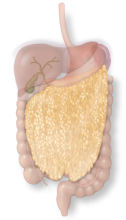

The omentum is a fatty apron that serves a protective role and helps filter immune responses to gut bacteria.